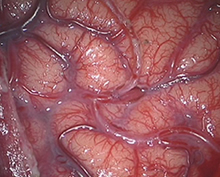

頭皮の血管を脳表の血管に吻合する。

<実際の手術>

<術後画像検査>

術後はバイパス血管が脳内に向かって出現している(赤丸印)。